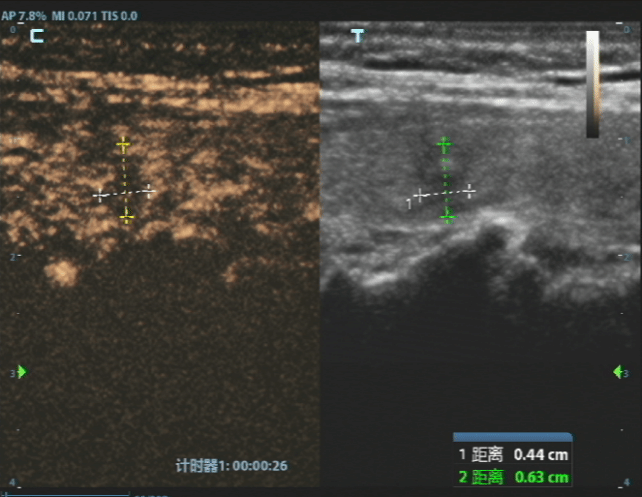

消融前病灶

经过严谨评估,刘女士首先接受了甲状腺穿刺活检。病理结果证实了最坏的猜想——甲状腺乳头状癌。但紧随其后的详细评估,却带来了好消息,结节微小、单发、未转移、未侵犯包膜,完全符合射频消融治疗的黄金指征。

这意味着,不用传统开刀手术,仅通过一根细针,在超声的实时引导下,就可以用热量精准“消灭”这个病灶。主管医师杨波波向刘女士详细解释,“它能最大程度保留你的甲状腺功能,脖子上不会留疤,恢复也快,更无需因此终身服药。”